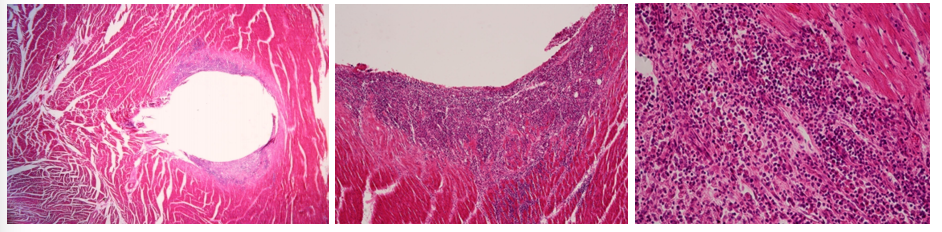

Fibrosis myocardii

Description: Myocardium of the heart is locally substituted by mature fibrous tissue with bright staining (some places fatty tissue is present). Substitution of damaged myocardium (infarct, necrosis, inflammation) by repair, when granulation tissue mature to highly-differentiated connective tissue (healing process).

Etiology: Damage from infarct, necrosis of different etiology and inflammation

Pathogenesis: Healing process begins with macrophages removing dead cells and debris, eliminating inflammatory exudate and dead tissue. The myocardial defect is filled with granulation tissue- fibroblasts, collagen-producing cells, and new blood vessels. This tissue matures into a fibrous scar, depositing collagen fibers for structural support. This restores structural integrity, but there may be a loss of function due to the replacement of specialized cells, determined by extent of loss.